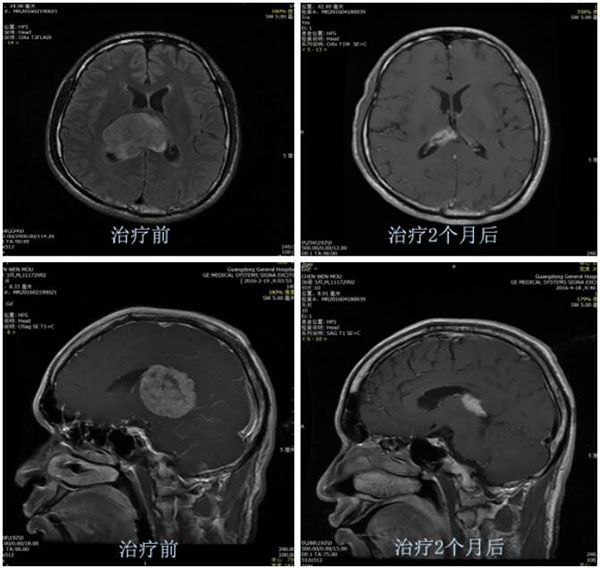

典型病例:肺癌脑转移,病灶虽然较大,但位于重要功能区(丘脑),不宜选择手术切除,

经靶向治疗2个月后病灶明显缩小,效果非常好。